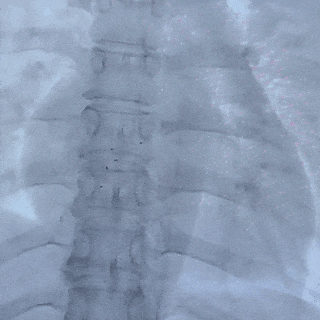

撤出成型线后,前抵鞘管,逆时针旋转钢缆,5个Mark点相对位置不变,封堵器释放成功

释放后影像

最后封堵器盘面稳固扣合,形态扁平且位置良好,封堵成功